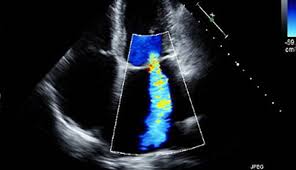

심장 초음파로 알 수 있는 병 ⑥ 폐고혈압

심장 초음파는 심장에서 폐로 가는 혈압 상태도 간접적으로 확인할 수 있습니다. 폐고혈압이 있는 경우 우심실에 부담이 가해지며, 이 역시 심장 초음파로 알 수 있는 병 중 하나입니다. 숨이 차거나 계단 오르기가 힘들다면 의심해볼 수 있습니다.